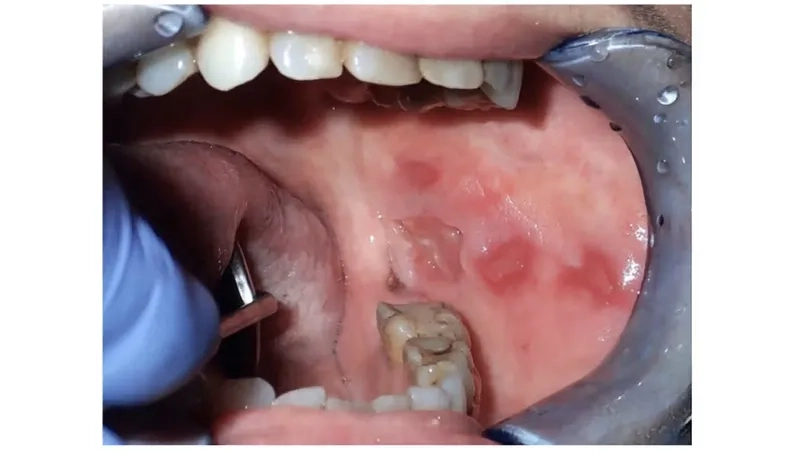

Clinical oral cancer pictures for awareness

• One of the most common mouth cancer symptoms is a sore, ulcer, or irritation in the mouth or on the lip that does not heal.

• Be aware of red or white patches (erythroplakia or leukoplakia) on the lining of your mouth, gums, or as part of tongue cancer symptoms.

• Other signs include a lump, difficulty chewing or swallowing, persistent pain or numbness anywhere in the mouth, or a change in your voice.